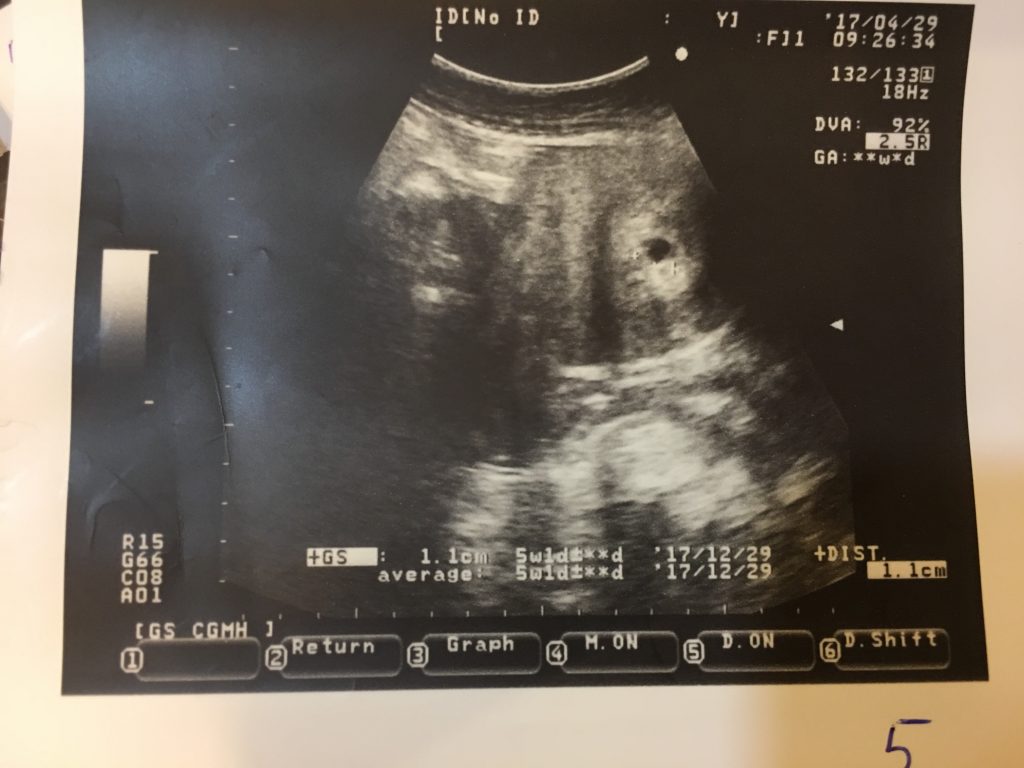

孕期 1 3個月baby每月成長記事 涼母與寶貝的生活 幸福是在點點滴滴中 痞客邦

心情故事 每個經歷都變成無價資產 懷孕初期第七週的變化 妞媽lisa Li X 妞爸169 分享愛

心情故事 每個經歷都變成無價資產 懷孕初期第七週的變化 妞媽lisa Li X 妞爸169 分享愛

準媽媽日記2 看到胎囊的安心 Qmi Guaiso Justin Brian 隨意窩xuite日誌

心就在這裡停泊吧 藏了好久的祕密 肚子裡的小胎寶滿三個月了 孕4週 孕8週

6週照到雙胚囊 但胚囊只有5週大 還沒有囊黃 胚胎 及心跳 Babyhome親子討論區

懷孕 孕囊 是怎麼變化的 孕囊 發育慢怎麼辦 每日頭條

懷孕 人生另一個開始 小米s ღღٱ 越夜越美麗 隨意窩xuite日誌

心就在這裡停泊吧 藏了好久的祕密 肚子裡的小胎寶滿三個月了 孕4週 孕8週

5w胎囊幾大 懷孕前後 Baby Kingdom 親子王國香港討論區

孕早期孕囊 胚芽 胎心完美三部曲 每日頭條

孕6周胎芽發育簡報 B超單上寫有這 四物 表明 坐胎 穩定 每日頭條

孕 6週 10週 戰戰兢兢的懷孕初期 依芙琳看世界 痞客邦

7w5 4w5 第一次產檢 5c9